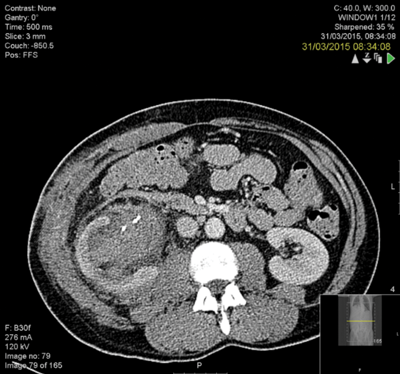

The kidney was grossly inflamed and it was very difficult to identify the anatomy. The surgeon considered a nephrectomy but persevered to complete the repair. The patient remained in hospital for two weeks postoperatively with low grade pyrexia and a CT revealed a clot in the collecting system and possible calyceal perforation (Figure 4) and extravasation. This was seen to have improved on a subsequent CT (Figure 5).

Figure 4.